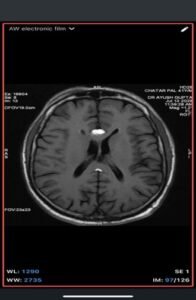

Imaging Findings-

- MRI

- T1-weighted: Hyperintense (fat signal).

- T2-weighted: Variable, usually hyperintense; may show chemical shift artifacts.

- Fat-suppressed sequences: Complete signal suppression confirms fat composition.

- Post-contrast: No enhancement.